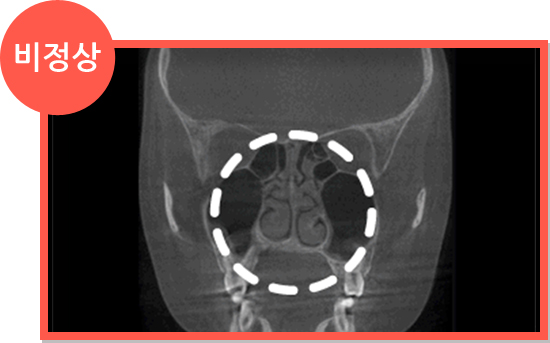

CT

CT

세계적으로 인정받는

Amorphous Silicon Flat Panel

센서를 사용하여 선명한 고화질로

환자의 상태를 볼 수 있어

정확한 진단이 가능한 CT로 진단

세계적으로 인정받는

Amorphous Silicon Flat Panel

센서를 사용하여 선명한 고화질로

환자의 상태를 볼 수 있어

정확한 진단이 가능한 CT로 진단